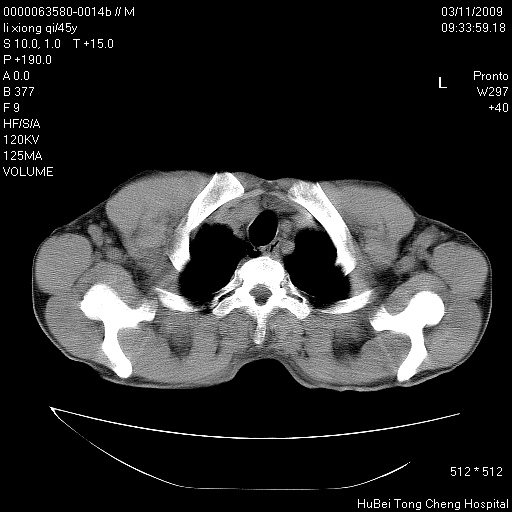

患者 男,45岁。胸痛,咳嗽伴痰中带血1月余。

临床诊断:肺结核?

胸部ct轴位平扫(层厚10mm,螺距1.5,重建间隔10mm),图像如下: